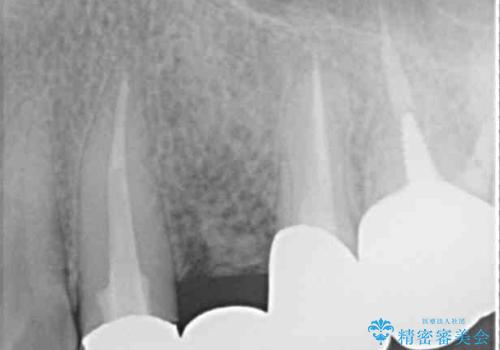

- 上下前歯のデコボコと銀歯のブリッジを気にして来院された患者様です。

装着されているブリッジを切断して矯正治療を行うことや、手間をかけずに早めに治療を終えたいとのことで、目立たないワイヤー装置による矯正治療を行うこととしました。

矯正治療後には切断したブリッジをオールセラミックブリッジに置き換えることとしました。